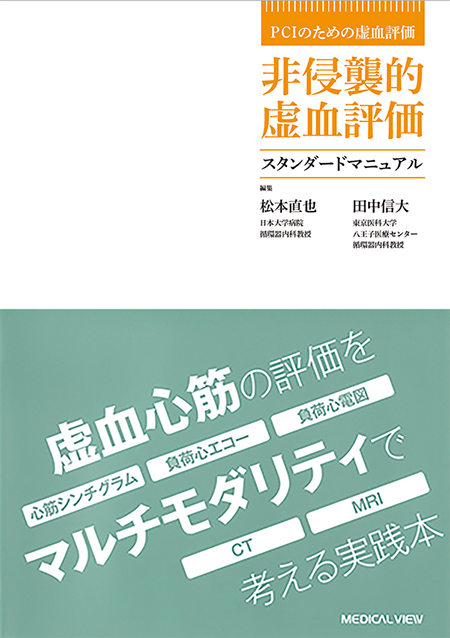

【誠実】 循環器医・放射線科医のための 江原省 | ゼロからわかる心臓MRI 医学一般

【誠実】 循環器医・放射線科医のための 江原省 | ゼロからわかる心臓MRI 医学一般

循環器医・放射線科医のための ゼロからわかる心臓MRI | 江原省,

循環器医・放射線科医のための ゼロからわかる心臓MRI | 江原省, 商品詳細ページ | メディカルブックセンター,

商品詳細ページ | メディカルブックセンター, 71yOet90uaL._AC_UF350,,

71yOet90uaL._AC_UF350,, m3電子書籍 | 循環器医・放射線科医のための ゼロからわかる心臓MRI,

m3電子書籍 | 循環器医・放射線科医のための ゼロからわかる心臓MRI, ziostation2」の心臓領域アプリケーション - 技術解説